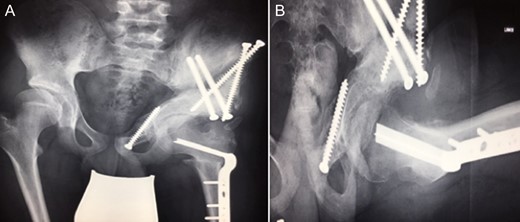

(A + B): (2008) (A) Hip reconstruction with open reduction, Tönnis triple pelvic osteotomy and shortening rotational varus osteotomy of the left femur demonstrating correct deep reposition in ap view. (B) Lauenstein view shows that the acetabular congruency over the femoral head is restored.